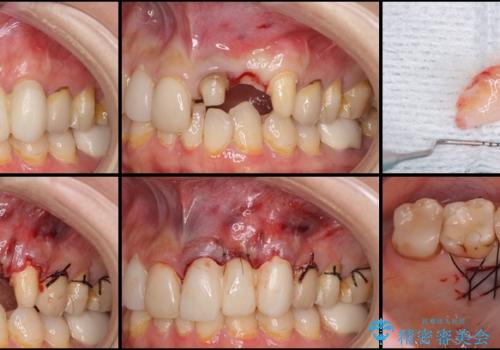

歯肉移植を用いた前歯のオールセラミックブリッジ

- 前歯が折れてしまい、ブリッジによる補綴治療を希望して来院された患者様です。

折れている前歯は抜歯をし、痩せてしまう歯肉は移植術により増大させることで審美面を回復した後、オールセラミックブリッジにて補綴することとしました。

インプラントかブリッジか悩むところでしたが、既に治療されている前歯のクラウン周りの変色が気になっていたため、ブリッジにより色調を合わせたオールセラミックを装着することを選択しました。

歯肉ラインや歯の形態、色調を整えることができ、患者様には大変満足していただきました。